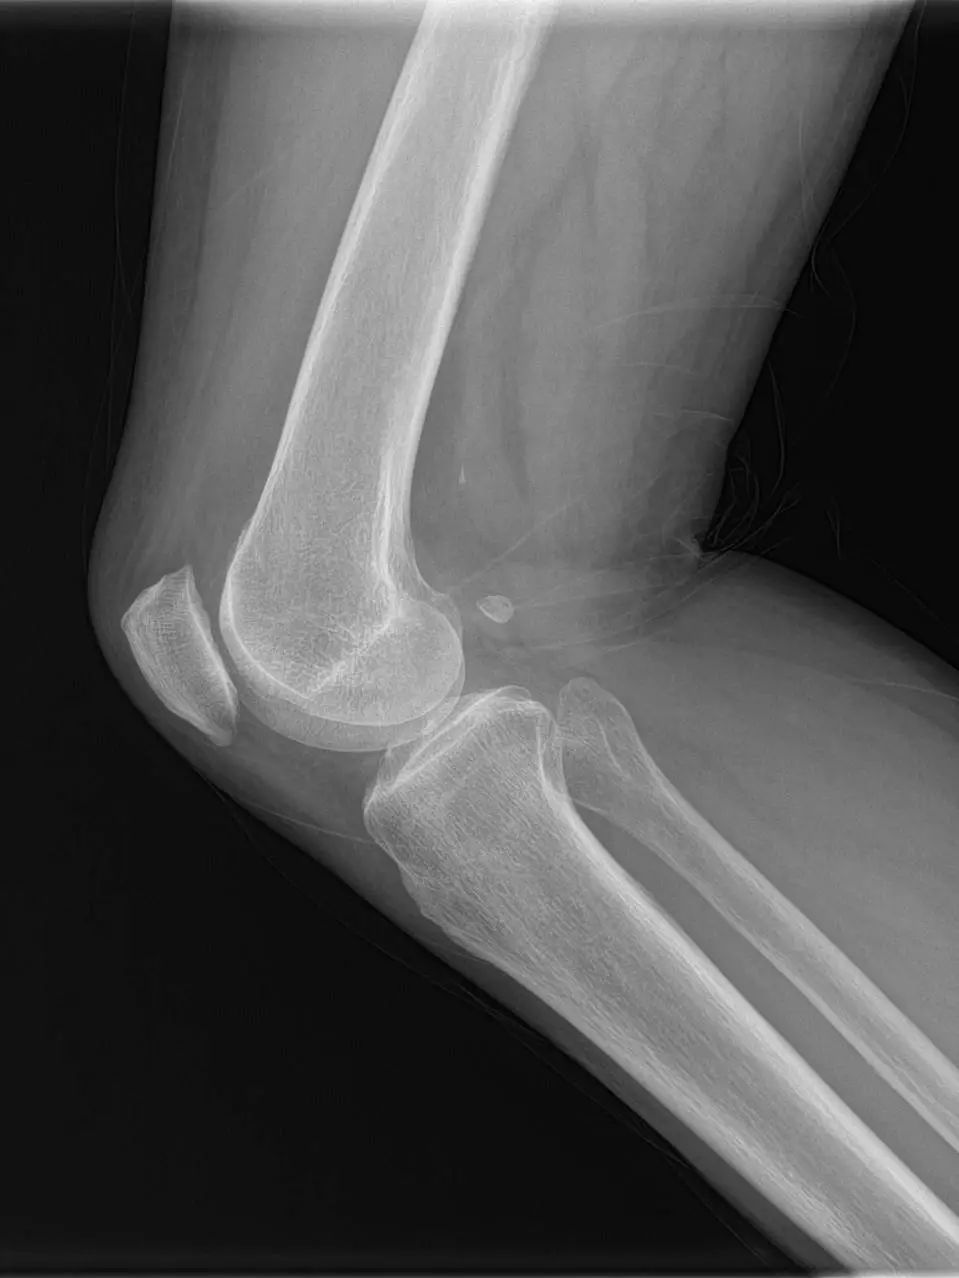

74岁的吕阿姨膝关节疼痛10余年,屈伸活动受限,外院就诊止痛药等保守治疗效果欠佳,拍片提示膝退行性骨关节炎。近日,她慕名来到上海市同济医院骨关节外科中心程飚主任门诊,程飚主任结合患者症状,影像学结果,体格检查,发现吕阿姨主要问题集中在膝关节内侧及髌股关节,膝关节外侧尚可。

为尽可能保留吕阿姨关节,程飚主任对定对吕阿姨进行膝关节部分置换手术,包括膝关节内侧单髁置换,髌股关节表面置换,尽可能减少膝关节截骨量,尽快恢复膝关节功能。吕阿姨术后第一天就开始下地走路了,她表示膝关节疼痛明显缓解,膝关节的活动范围也明显增加了,对程主任精准的手术治疗表示衷心的感谢。